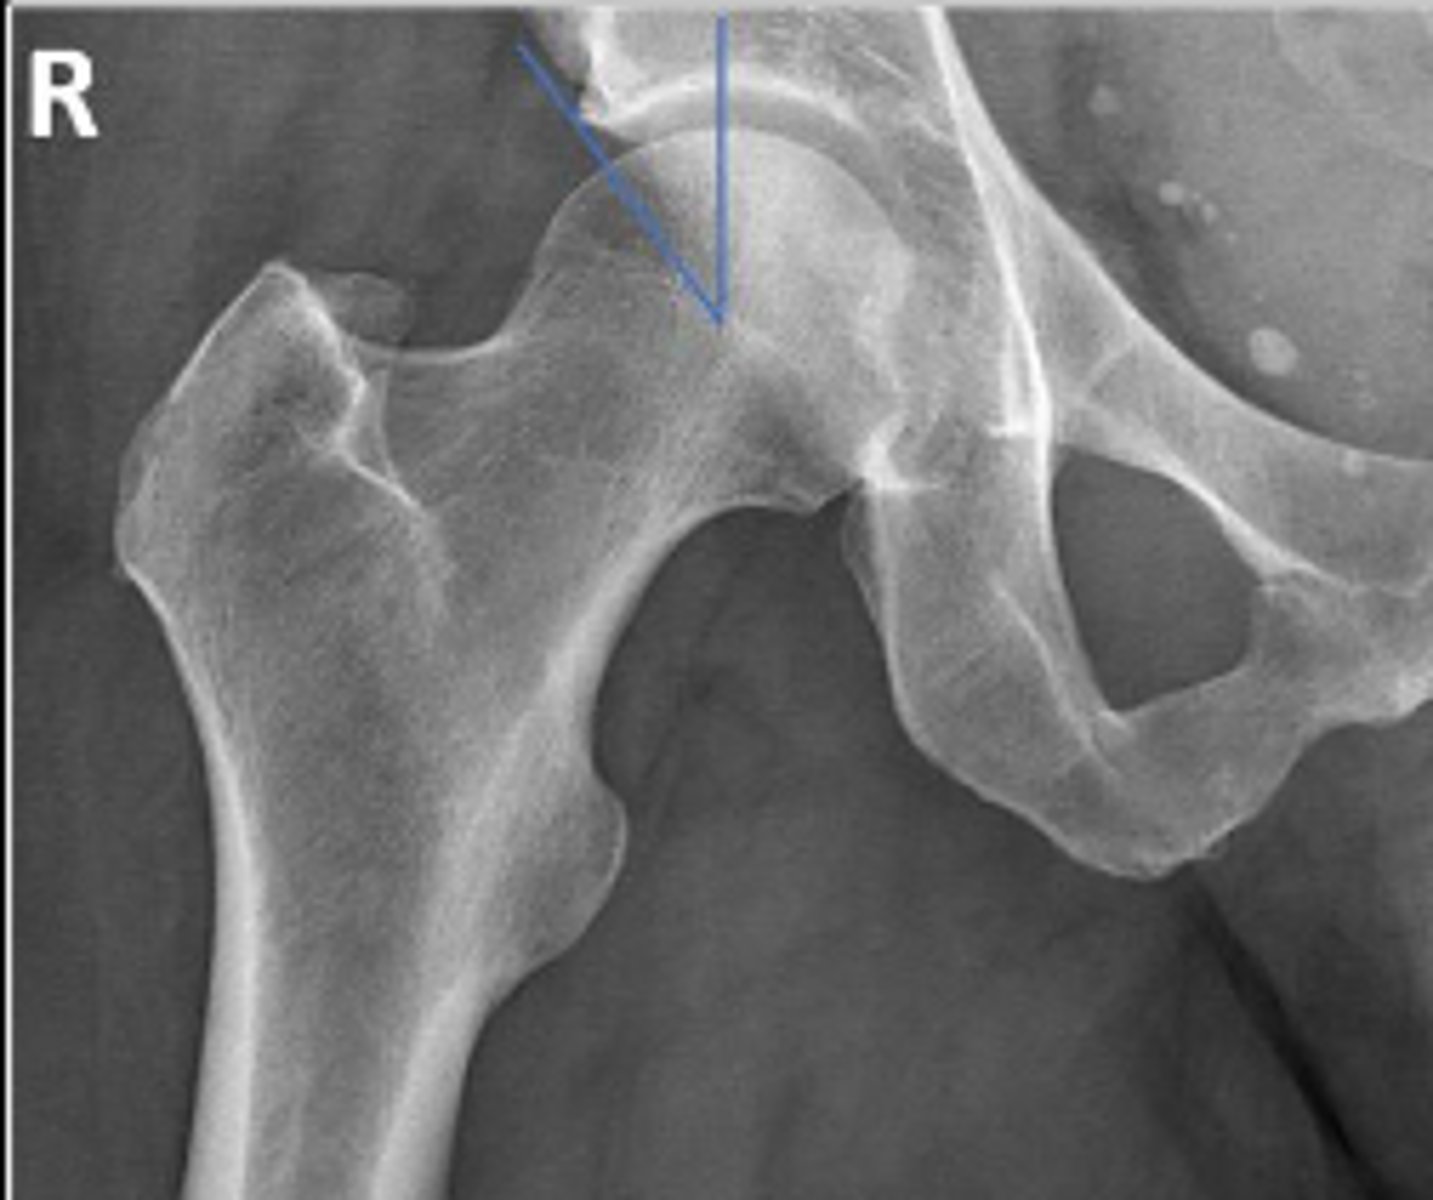

Right AP hip

What is the name of the radiographic view?

Intertrochanteric line of the right femur

What are the arrows pointing to?

Lesser trochanter of the right femur

Greater trochanter of the right femur

Right ischial tuberosity

Posterior rim of the right acetabulum

Anterior rim of the right acetabulum